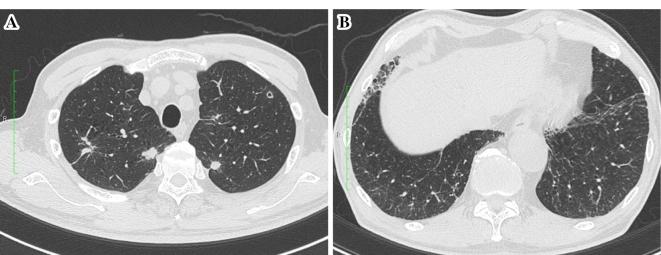

Although pneumothorax has been reported to be a major pulmonary adverse event in patients treated with pazopanib, a multikinase inhibitor, drug-induced interstitial lung disease (DILD) has not been reported. A 74-year-old Japanese man who received pazopanib for the treatment of femoral leiomyosarcoma and lung metastasis presented with dyspnea and fatigue. He had mild interstitial pneumonia when pazopanib treatment was initiated. Chest computed tomography revealed progressive bilateral ground-glass opacity (GGO) and traction bronchiectasis. We diagnosed DILD due to pazopanib. The patient's pazopanib treatment was interrupted and a steroid was administered. The symptoms and GGO were improved with treatment. Physicians should be aware of DILD due to pazopanib in patients with pre-existing interstitial lung disease.

虽然据报道气胸是接受多激酶抑制剂帕唑帕尼治疗的患者的主要肺部不良事件,但药物性间质性肺病(DILD)尚未见报道。一名74岁的日本男性因股部平滑肌肉瘤和肺转移接受帕唑帕尼治疗,出现呼吸困难和疲劳。开始帕唑帕尼治疗时他有轻度间质性肺炎。胸部计算机断层扫描显示双侧进行性磨玻璃影(GGO)和牵拉性支气管扩张。我们诊断为帕唑帕尼所致的DILD。患者的帕唑帕尼治疗中断并给予类固醇治疗。治疗后症状和GGO有所改善。医生应意识到在已有间质性肺病的患者中帕唑帕尼可导致DILD。